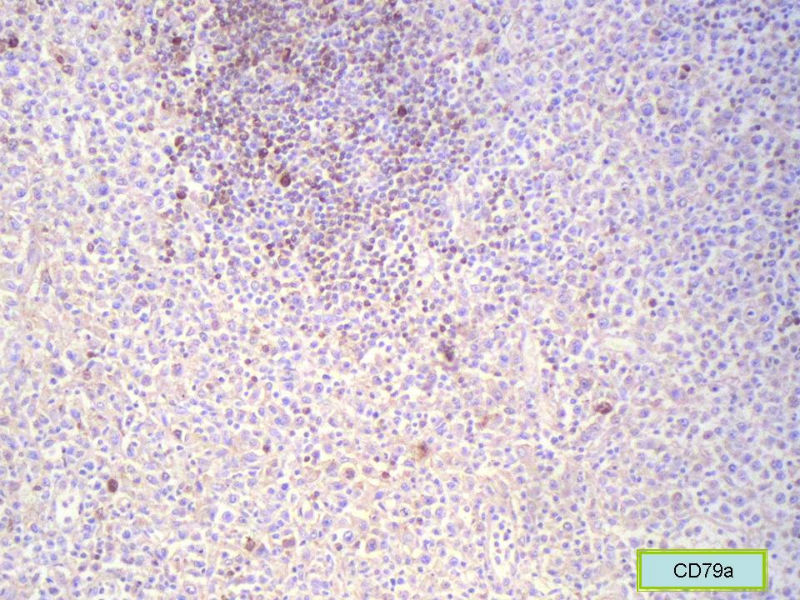

该患者可能存在病毒的感染,抑或是EB病毒的感染,包括CD30+的细胞在内,夹杂在组织细胞、小淋巴细胞之间的一些个大细胞是活化的淋巴细胞,表型看来属B细胞。整个形态呈反应性增生的形态。

标记CD68和溶酶体酶,可能显示组织细胞比较多。

总之,现有的图片显示的形态和IHC标记尚不足以诊断为淋巴瘤,除非有有基因重排的支持。

请看下图,显示的细胞比较杂,胞浆较丰富,胞核没有什么特别的异型性。没有促纤维增生反应和围血管生长表现,没有肿瘤性坏死,没有见到更多的核分裂,特别是病理性核分裂。因此认为,本例是淋巴组织反应性增生,可能是对病毒感染的反应。